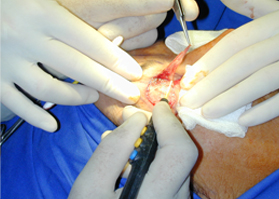

適用于細微、精細的切割如頭頸部,敏感部位皮膚的切割。

適合于皮下組織的切割和剝離。

特別是在運血較為豐富的部位。